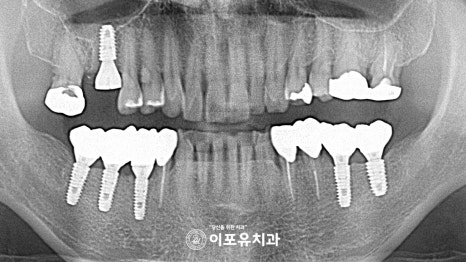

준비한 파노라마 사진에

어금니를 살펴보면

이차우식 및 치근단 병소, 치아 상실이 관찰됩니다.

이미 이가 빠져있는 곳들은

치조골 소실이 심하게 나타나 있는데

이런 곳들은 골이식을 동반하여

치조골을 충분히 채워준 뒤에 진행해야 됩니다.